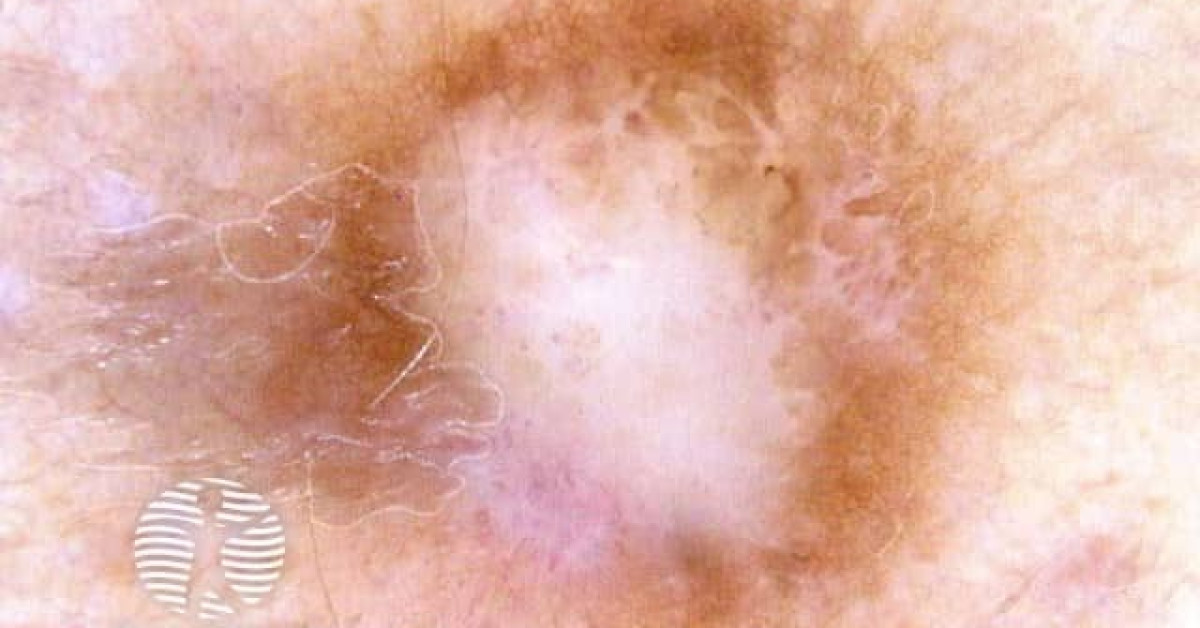

Дерматофиброма Фото После Удаления